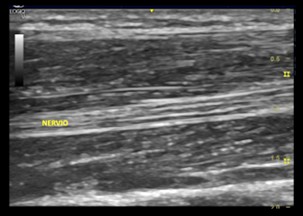

Al utilizar una proyección longitudinal durante la ecografía se muestran varias líneas paralelas hipoecogénicas que corresponden con los fascículos neuronales que discurren longitudinalmente dentro del nervio, separadas por bandas hiperecogénicas.  Estas bandas hiperecogénicas interfasciculares son el epineuro interno, y las bandas hiperecogénicas que definen los limites externos del nervio es el epineuro externo.

Imagen ecográfica 1.1 Eje longitudinal del nervio mediano en antebrazo.

En la proyección transversal se muestra un patrón reticular o en panal de abeja, compuesto por puntos hipoecogénicos incrustados en un fondo hiperecogénico; en el que las estructuras hipoecogénicas corresponden a los fascículos y el fondo hiperecogénico corresponde al epineuro interfascicular o interno.